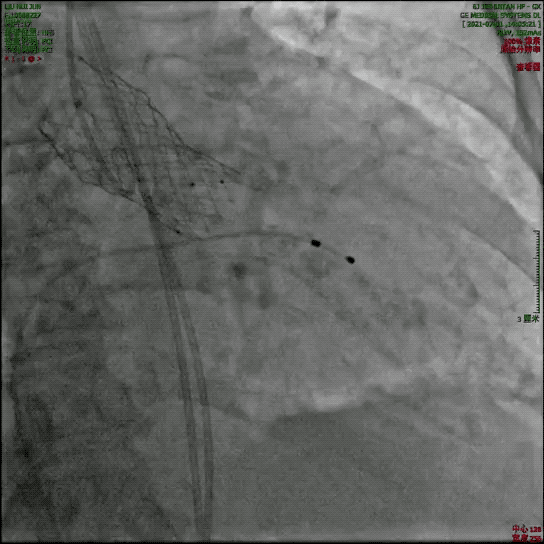

瓣膜释放过程

瓣膜完整形态